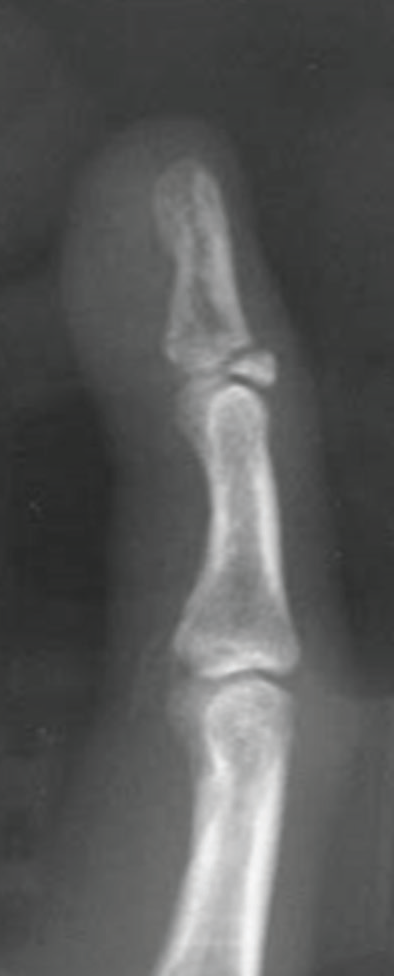

C. Ekstansör tendonun kemiğe yapıştığı yerde kopma kırığı oluşmuştur.

Yaralanmadan sonra hasta parmak ucunu kaldıramıyorsa, tırnak altında kan toplanmışsa veya tırnak kökünden kopmuşsa hekime başvurmalıdır. Küçük bir şişlik veya morarma olan yaralanmalarda bile kırık söz konusu olabilir. Parmakta şekil bozukluğuna neden olan bir kırık olup olmadığını göstermek için röntgen veya ultrason görüntüleri kullanılabilir. Açıkta kemik bulunan veya tendonu kesilmiş çekiç parmakları, enfeksiyonu önlemek için acilen tedavi edilmelidir.